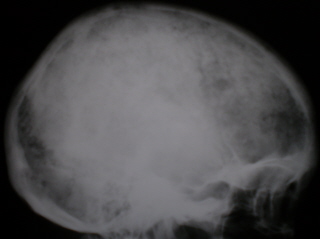

Характерным для миеломной болезни является выраженный деструктивный процесс в костях свода черепа.

Однако известны случаи, когда в костях свода черепа при миеломной болезни изменения не выявлялись.

Иллюстрации 4, 5 – очаги деструкции костной ткани в костях мозгового черепа округлой формы.